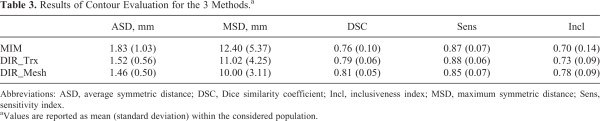

Qualitative results of contour propagation using MIM, DIR_Trx, and DIR_Mesh are presented in Figure 2, showing a good agreement between the manual reference contours and the propagated ones, without evident differences among the 3 methods. Quantitative results of contours evaluation are reported in Table 3. Average symmetric distance, MSD, and DSC indices calculated on both PGs for all patients and for all 3 considered DIR methods are plotted in Figure 3. DIR_Mesh presented the lowest average values of ASD and MSD and the highest average value of DSC over the population among the 3 methods, although nonsignificant (P values of the nonparametric Kruskal-Wallis test = 0.57, 0.40, and 0.27 for ASD, MSD, and DSC, respectively). The average propagation errors with respect to the reference contours are lower than the voxel diagonal (2 mm), and DSC is around 0.8, generally considered as the threshold for good agreement.